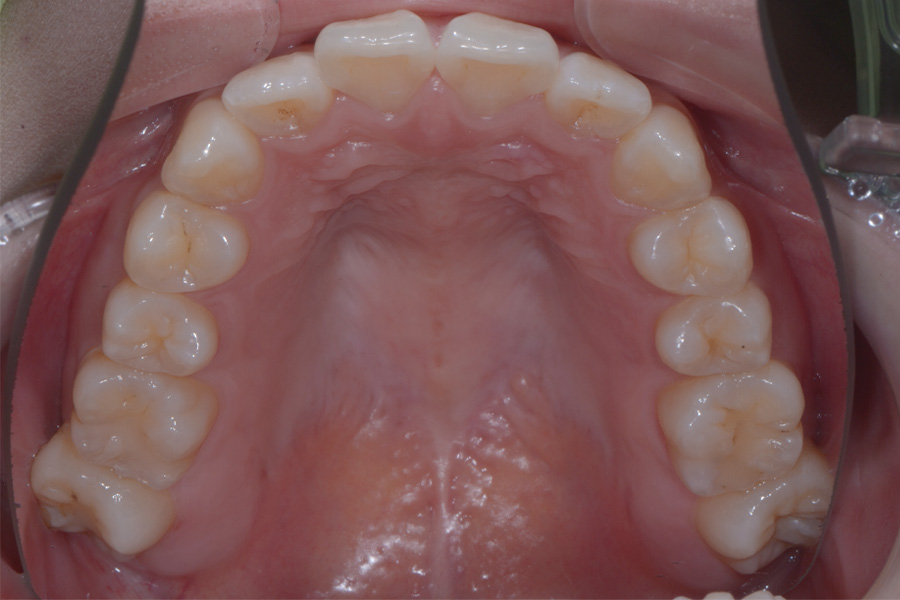

【20代女性】

飛び出ている2本の歯を引っ込めて

下の捻じれている歯を並べたい

治療後

主訴 飛び出ている2本の歯を引っ込めて下の捻じれている歯を並べたい

治療内容 ハーフリンガル矯正(上顎裏側・下顎表側矯正)